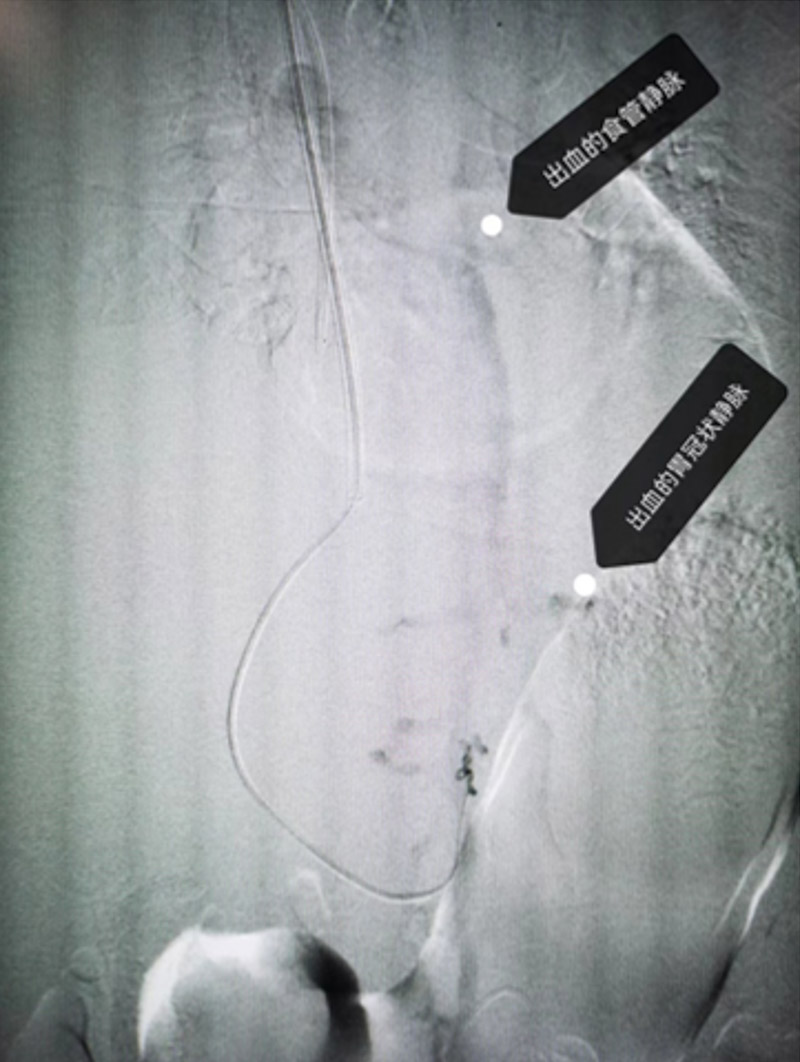

患者血素色持續下降,血管外科主任霍鑫迅速帶領介入團隊開展急診手術,根據CT判定穿刺位置,從肝內肝靜脈穿刺進入門靜脈,利用DSA及彩超定位,在門靜脈跟肝靜脈之間放一個血管支架,建立一個新的分流通道——高壓的門靜脈血流直接經支架分流道向下腔靜脈,2個半小時后,手術順利完成。患者的靜脈壓力從術中的38cmH2O(正常12-24cmH2O),降至術后的23cmH2O。